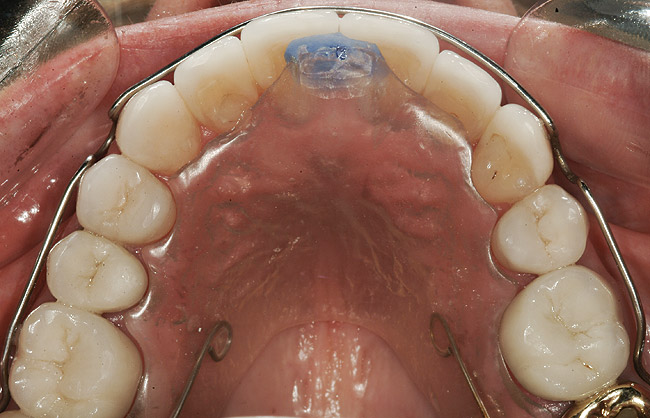

FUNCŢIONAL: La majoritatea dinţilor posteriori ai pacientei ce erau restauraţi cu coroane (fig. 6, 7) era importantă interpretarea minuţioasă a istoricului pacientei şi a rezultatelor evaluării ocluzale. Coroanele din aur de la nivelul 1.7. şi 1.4. prezentau orificii de uzură pe suprafeţele ocluzale, cu semne de minimă uzură pe celelalte coroane posterioare şi la dentiţia naturală. Era evidentă o uzură moderată pe coroana din aur a molarului 4.7.

ETAPA aII-a: ORTODONŢIE COMPREHENSIVĂ

Pacienta a fost îndrumată pentru evaluarea ortodontică comprehensivă. Aşteptările tratamentului constau în nivelarea planului ocluzal maxilar, corectarea rotaţiilor şi a angrenajelor inverse şi alinierea dinţilor, cu îmbunătăţirea nivelurilor şi funcţiilor tisulare. Obiectivul primar al terapiei ortodontice era stabilirea poziţiei dentare ideale pentru tratamentul restaurator (fig. 10- 12).